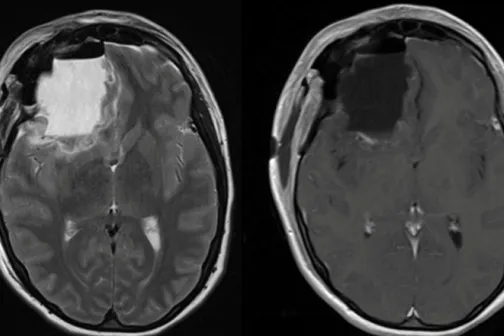

Imagine 01/06/2022 -21:21 Sănătate Misterul din New Jersey. Peste 100 de absolvenți ai aceluiași liceu au făcut o formă rară de cancer cerebral